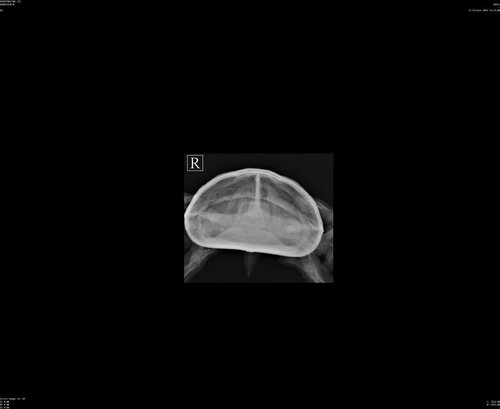

Обратились в клинику. Сделали рентген, доктор сказала, что ничего не насторожило. Есть немного обезвоживание. Кровь пока не сдавали. Когда посмотрела горло, сказала, что там налет. И выписали Байтрил 5%, по 0,04мл каждый день 14 дней. И раствор Рингера  8мл раз в два дня 7 дней. Можно ли прокомментировать назначение? Т.к. на форуме говорится, в основном,  о Байтриле 2,5%, и не каждый день. Пока поставили в клинике один раз, и два раза я дома. Но, похоже, не разобралась со шприцом, поставила оба раза по 0,02мл, а не 0,04мл

Врача звали Морозова Валерия Сергеевна. Ничего плохого сказать не могу, черепаху смотрели очень внимательно. Сначала он никак не хотел открывать рот. Посмотрели на рентгене, ничего страшного не увидели. Нам предложили дополнительно сдать кровь, но я сразу не была готова. Тогда решили, что еще понаблюдаем. Т.к. предположили, что не хватает УФ, потому что лампу мы только накануне приобрели. И под конец приема удалось заглянуть ему в рот. И Валерия Сергеевна сказала, что там все с налетом. Предположила инфекцию. И сказала, что с таким горлом уже сразу назначает антибиотик. Тем более, он сразу и запищал, как горло задели. А уж сдавать кровь или нет - это наш выбор. Я просто сомневаюсь насчет Байтрила 5% - сколько в итоге колоть? Если по 0,04мл, то это через день тогда? 14 уколов? Или лучше все-таки купить 2,5%? Тогда по сколько колоть?